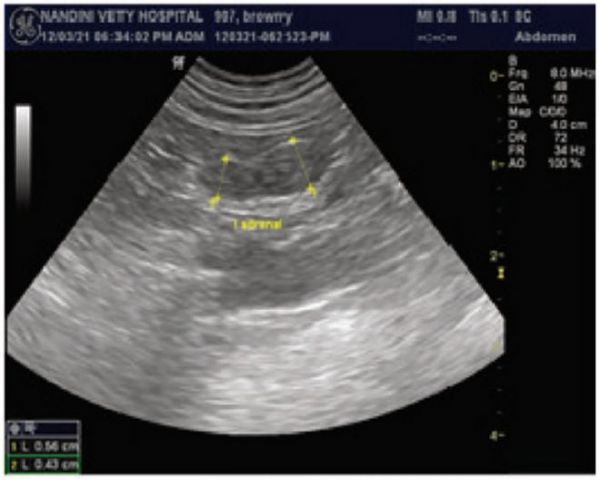

• 猫科动物的肾上腺呈椭圆形或豆状。它们两侧对称,相对于周围腹膜后脂肪为低回声。皮层和髓质无法区分。肾上腺矿化偶然可发现。

图4 德国牧羊犬的超声图,肾上腺为长而薄的低回声结构,边界为高回声。

右肾上腺(A)呈饼状,左肾上腺(B)呈细长结构。正常肾上腺的宽度从4.2到6.0 mm不等(C)。